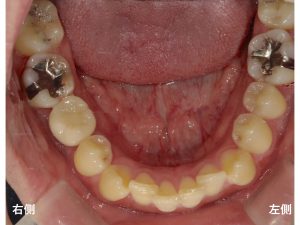

以下が初診時です。

下顎の噛む面から写真を撮った状態です。

右側の歯が欠損しています。